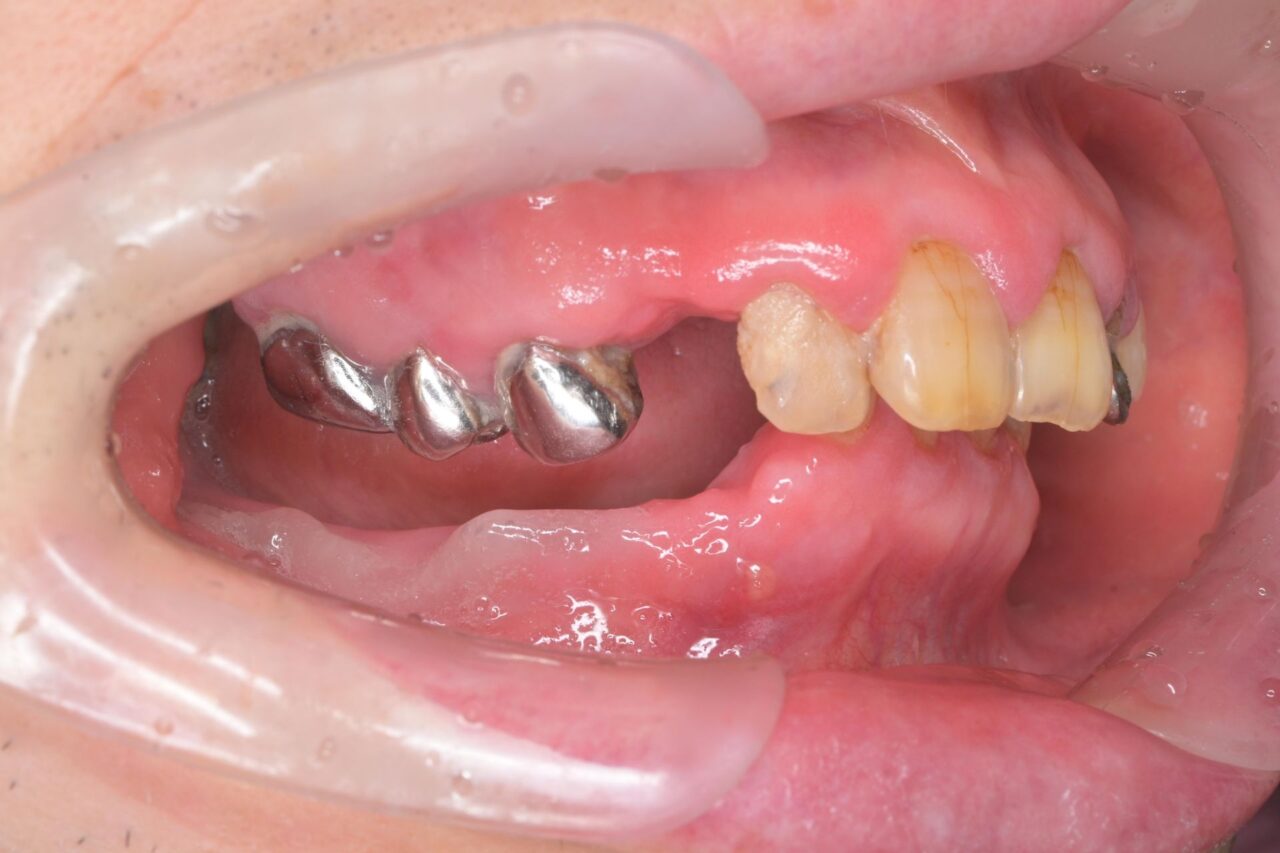

右側

右下には全く歯がありません。

これでは奥歯でお肉が噛めません( ;∀;)